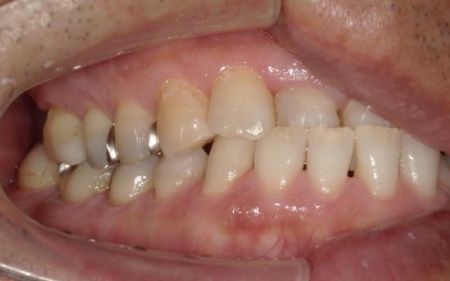

40代男性 虫歯治療やインプラント治療で口腔内全体を修復したあと部分矯正で噛み合わせを改善した症例

拝見したところ、複数の歯に虫歯が見られました。また、過去に治療した詰め物や被せ物が合わなくなっている部分や、歯が欠損している部位もあります。

・右上奥歯

一番奥の歯が欠損し、その手前の歯は詰め物の内部で虫歯が進行しています。

・右下奥歯3本

噛む面や歯間に虫歯が見られ、歯が欠けている部分もあります。

・インプラント治療

保存が難しい左下奥歯(第2大臼歯)と、すでに欠損していた右上の部位については、インプラント治療を行います。インプラント治療とは、顎の骨に人工歯根を埋め込み、そこに人工歯を取り付ける治療方法です。

右下奥歯3本と左下奥歯2本については、虫歯を除去したあとに歯科用樹脂を直接歯に盛り付けて形を整える「ダイレクトボンディング」を行います。